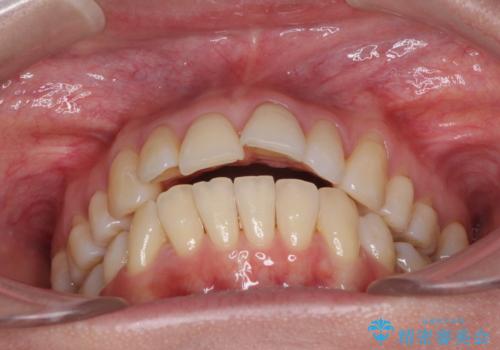

- 上の前歯の出っ歯を治したいとのことで来院された患者様です。

後戻りによる再矯正というもともあり、インビザラインを希望されていました。

上顎の歯は後方移動とIPR(歯と歯の間を削る)によって口元が引っ込むように、下顎は歯列全体の拡大とIPRによって上顎とバランスよく咬み合うように設計し、インビザラインにより治療を行うこととしました。

治療を開始して暫くして、勤務先から2年以上帰国することができず、それまでの移動がほとんど後戻りしてしまい、帰国後に再度後戻りをリカバリーするための治療を行うこととなりました。

5年以上の治療期間がかかりましたが、気になっている部分を改善することができました。